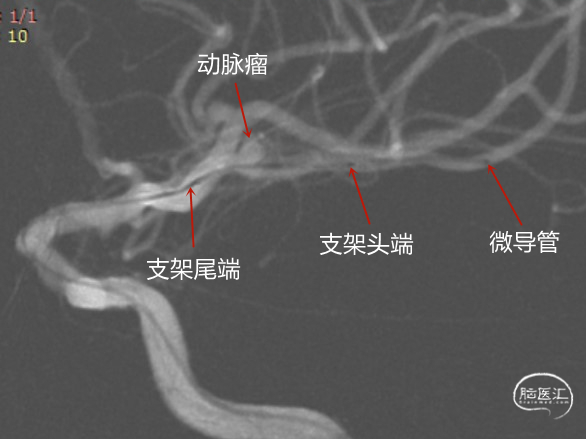

微导管顺利到位,若再上微导管担心指引导管过低,支撑力不够,遂释放3.0mm*15mm Atlas支架,后撤SL-10微导管穿网孔栓塞动脉瘤。

术中释放3.0mm*15mm Atlas支架到位后,后撤预塑45°的SL-10微导管,使用微导丝引导轻松穿网孔进入动脉瘤。